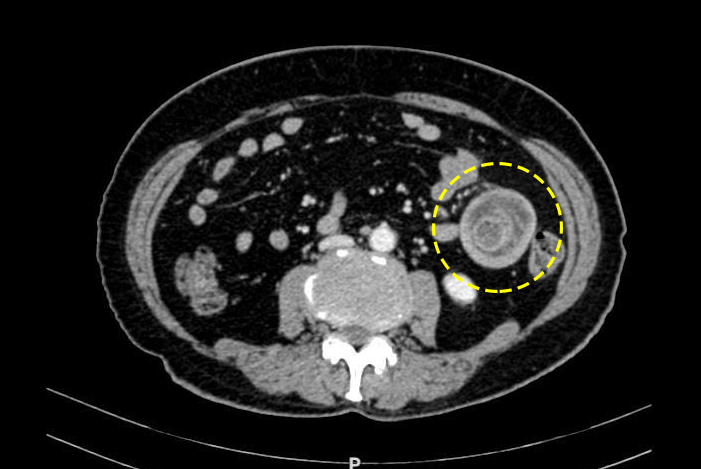

Physicians can detect intussusception during a clinical examination. Abdominal ultrasound may reveal intussusception, but its sensitivity is lower than CT due to interference from intestinal gas. CT scans also help pinpoint the obstruction's location, assess vascular status, and guide the identification of the underlying cause.

![]() |

Intussusception mass on a CT scan. Photo: Tam Anh General Hospital |